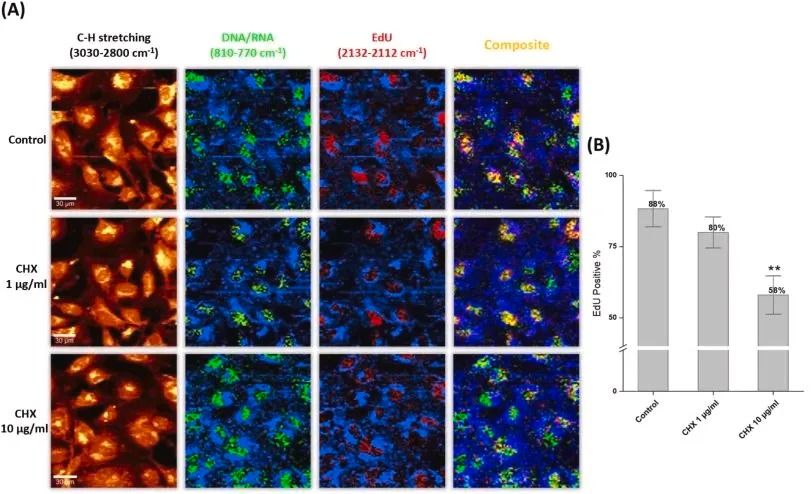

我們經常被一個難題所困擾:如何在精準標記DNA復制活躍細胞的同時,保持細胞結構的完整性?傳統BrdU檢測法雖然廣泛應用,但其依賴的DNA變性步驟如同一把雙刃劍——在暴露抗原表位的同時,也破壞了細胞的原始形態和生物分子網絡。今天普拉特澤生物繼續帶大家一起學習新實驗~

在細胞增殖過程中,當DNA進入合成期(S期),EdU能夠替代天然胸苷摻入新合成的DNA鏈中。與傳統BrdU不同,EdU的檢測不依賴大分子抗體識別,而是通過“點擊化學”(Click Chemistry)實現——乙炔基與熒光標記的疊氮化物在銅離子催化下,形成穩定的三唑環。

高靈敏度與免變性的技術優勢

無DNA變性:保護樣本完整性的技術突破

●傳統BrdU檢測的致命瓶頸在于DNA變性步驟:鹽酸處理、高溫或酶解不僅耗時(≥4小時)更導致:

●細胞核形態破壞:核膜皺縮、染色質彌散,影響成像質量.

●抗原表位損毀:難以與胞內蛋白標記(如Ki-67、磷酸化組蛋白)聯用.

而EdU檢測徹底摒棄了變性需求。通過溫和的固定透化處理(4%多聚甲醛+0.5% Triton X-100),細胞三維結構、表位完整性和DNA高級結構均得以保全。這不僅讓細胞核邊緣清晰可見,更開啟了多參數分析的大門。

將EdU檢測與BrdU流程并置對比,其效率優勢一目了然:

●步驟減少40%:從BrdU的約10步縮減至6步核心操作